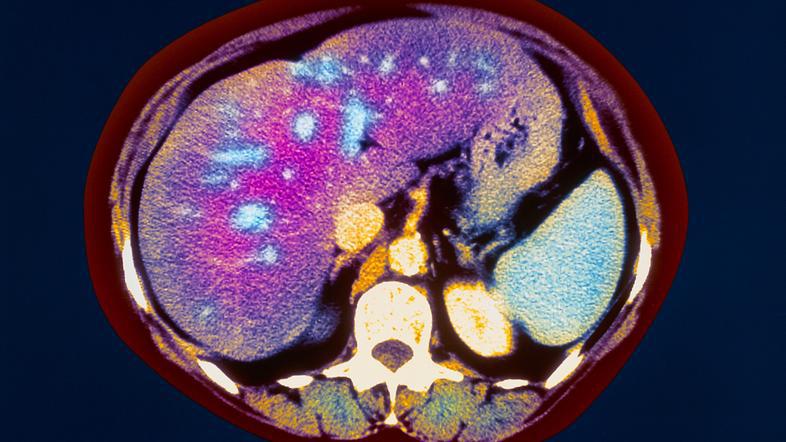

Čeprav imajo sposobnost obnove, jih lahko prizadenejo številne bolezni.

Jetra so največja žleza v telesu – na dan proizvedejo skoraj liter žolča, ki v črevesju sodeluje pri razgradnji maščob. Poleg tega imajo še številne druge funkcije, kot so na primer presnova beljakovin, maščob, ogljikovih hidratov in številnih zdravilnih učinkovin.

Čeprav imajo sposobnost obnove, jih lahko prizadenejo številne bolezni. Simptomi in znaki bolezni jeter so lahko dolgo prikriti ali nejasni, velikokrat je diagnoza postavljena, ko bolezen že zelo napreduje, zato je pri ohranjanju zdravih jeter ravno preventiva izrednega pomena, so pred letošnjim dnevom slovenskih lekarn poudarii farmacevti, ki so se letos osredotočili na zdravje jeter.